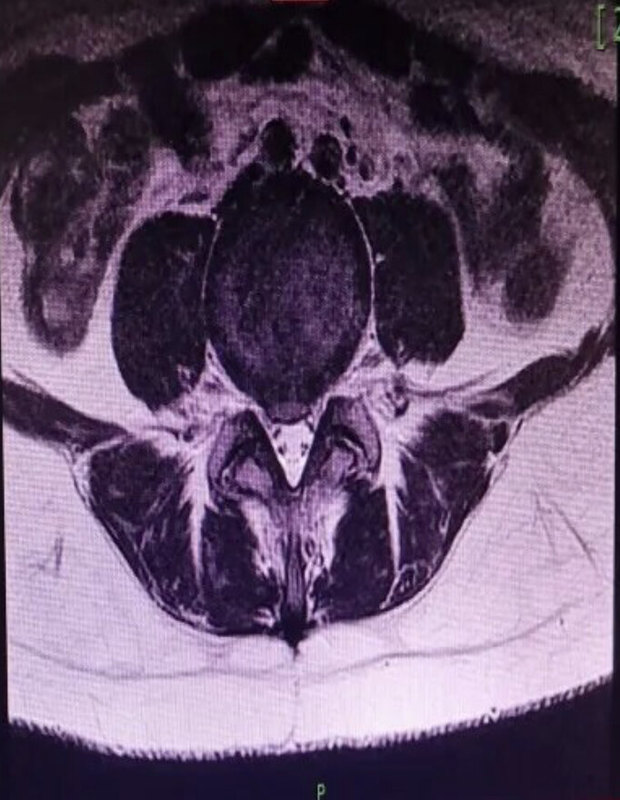

說起腰痛,很多人都經(jīng)歷過,但是都是怎樣治療的呢?貼膏藥,吃止疼片?今天我們先從一個(gè)腰痛患者的經(jīng)歷說起。門診最近來了一位三十歲的年輕媽媽,別看她年輕,她可是一位特別“突出”的老病人,這次不明原因又開始鬧腰痛了。在就診之前用她自己的話來說是:“翻身疼、坐立疼,走路時(shí)身體不能直立,身體向右側(cè)彎,打噴嚏和咳嗽會(huì)加重疼痛,穿鞋、刷牙、洗臉受限,彎不下腰”,為明確病因做了腰椎核磁共振檢查。這么一看是挺“突出”的啊,但這個(gè)病人僅表現(xiàn)為腰痛,明顯影像與癥狀不成正比!這是為什么呢?眾所周知,椎間盤突出癥是一種慢性疼痛性疾病,癥狀主要由椎間盤對(duì)相應(yīng)神經(jīng)的直接壓迫而產(chǎn)生的,因此分為頸椎、胸椎、腰椎間盤突出癥。一般通過臨床癥狀和影像學(xué)檢查確診,治療的根本原則是解除椎間盤對(duì)相應(yīng)神經(jīng)的壓迫。但有一種椎間盤突出是不容易看到的,那便是盤源性疼痛綜合征,這一類疾病是以椎間盤嚴(yán)重退行性改變?yōu)橹饕∫蛞鹋R床癥狀的疾病。該病的癥狀多變且詭異,疼痛往往不按照神經(jīng)分布而發(fā)生其中最常見的癥狀是腰腿痛,其次便是頸肩痛。隨著科技的進(jìn)步和生活壓力的增加,這一類疾病在臨床診療中逐漸增多和年輕化,同時(shí)由于盤源性疼痛綜合征的診斷相對(duì)困難,經(jīng)常發(fā)生誤診和漏診,臨床中很多反復(fù)不愈的腰肌勞損、坐骨神經(jīng)痛、肩周炎、腕管綜合征其實(shí)都是椎間盤退變搞的鬼??赐晟厦娴膬?nèi)容后您是不是又有新的疑惑?什么是椎間盤退變啊?它怎么就退變了?其實(shí)這個(gè)問題很好解答:我經(jīng)常拿椎間盤比作“餡餅”,中間的“餡兒”就是椎間盤的髓核,外面的“皮兒”就是就是椎間盤的纖維環(huán)。正常情況下這個(gè)“餡餅”的“皮兒”是非常致密的,它包裹的“餡兒”不會(huì)輕易的“漏”出來的。但是隨著年齡的增長和椎間盤壓力的增加,椎間盤會(huì)不同程度的發(fā)生退變。主要表現(xiàn)為“餡兒”失水,“皮兒”老化破裂,而漏出的這個(gè)“餡兒”又是刺激性較強(qiáng)的物質(zhì),刺激周圍產(chǎn)生炎性物質(zhì)和血管異常增生,而這部分異常增生的血管團(tuán)在核磁上變現(xiàn)為椎間盤高信號(hào)區(qū)(High-intensityzone,HIZ),它們通過刺激神經(jīng)根而引發(fā)疼痛。簡而言之就是“餡餅”變老、變干,出現(xiàn)裂縫,造成疼痛。而這一類型的疼痛通常影像學(xué)表現(xiàn)并不嚴(yán)重,呈現(xiàn)影像與癥狀不成正比的情況,因此盤源性疼痛又被稱為“看不見的椎間盤突出癥”。明白了上面的內(nèi)容,那我們?cè)僬J(rèn)識(shí)一下退變,直接上圖大家可能理解得更容易一些。正如這張腰椎核磁共振影像所示,藍(lán)色框中的椎間盤為正常椎間盤,呈中間“亮”,四周“暗”的表現(xiàn),其中亮的部分為健康的髓核組織,也就是我剛才說的“餡兒”,髓核中水的比重大,因此呈現(xiàn)發(fā)亮狀。而紅色框中的椎間盤變明顯變“黑”,臨床中成為“黑盤征”,是椎間盤退變的一種表現(xiàn),代表髓核失去了水分,因此核磁共振檢查中呈現(xiàn)暗黑色。這張圖中顯示的是纖維環(huán)(也就是“皮兒”)破裂后沿著裂口異常增生的血管團(tuán)。這些血管團(tuán)在核磁上表現(xiàn)為椎間盤高信號(hào)區(qū)(High-intensityzone,簡稱:HIZ)?,F(xiàn)在我們?cè)賮砜匆幌逻@位年輕患者的核磁影像圖片,您能發(fā)現(xiàn)問題了嗎?那么這位患者癥狀這么重,我們是如何治療的呢?首先患者的椎間盤屬于中心型突出,對(duì)神經(jīng)根的壓迫較輕,不易表現(xiàn)出神經(jīng)反射癥狀,即腿疼。其次HIZ局部的壓力增高,刺激局部小交感神經(jīng)產(chǎn)生疼痛信號(hào),引發(fā)疼痛,進(jìn)一步增加炎癥因子和致痛物質(zhì)的釋放。周而復(fù)始。若無法有效打破惡性循環(huán),病癥可能朝著惡化嚴(yán)重的方向一去不返。最后患者表示疼痛部位很深,經(jīng)詳細(xì)查體后發(fā)現(xiàn)患者的腰肌基本正常,沒發(fā)現(xiàn)明顯的疼痛點(diǎn),屈伸運(yùn)動(dòng)也屬大致正常范圍。在充分和患者交代病因及各種治療方法后,最終我們決定采用超聲引導(dǎo)下微創(chuàng)注射治療,針對(duì)該患者的病情及癥狀共治療了三次,并收到了非常滿意的治療效果。最后再說一下如何預(yù)防?防大于治,是疾病治療的根本。椎間盤退變是無法避免的,但我們可以通過適當(dāng)?shù)氖侄螠p緩?fù)俗儯苊馔俗冃纬杀P源性疼痛,大部分平時(shí)注意保養(yǎng)的朋友,都可以平穩(wěn)地度過這一時(shí)期,因此疾病不可怕,預(yù)防才是關(guān)鍵!1.避免勞累:現(xiàn)代生活節(jié)奏加快,壓力增大導(dǎo)致高危人群長時(shí)間保持不良體位是頸椎、腰椎間盤退變的重要原因,充分休息避免勞累是預(yù)防該疾病的重中之重。每小時(shí)放松頸部,勤抬頭,少低頭,平時(shí)盡量挺直腰背,不駝背,不哈腰,是預(yù)防疾病的原則。日常生活中要注意合理安排時(shí)間,避免給頸椎和腰椎帶來壓力。2.不睡高枕:俗話講高枕無憂,但對(duì)于該疾病的預(yù)防,這句話是不對(duì)的。高枕會(huì)在一定程度上的改變頸椎生理曲度,對(duì)頸椎是一種損傷。選擇合適的枕頭是使頸部充分休息的先決條件。建議選擇符合頸椎生理曲度的枕頭。3.腰部支撐:軟床,沙發(fā)等都是不建議使用的。在休息時(shí)建議對(duì)腰部進(jìn)行支撐,最簡單的辦法就是在腰后部墊一薄枕,維持腰部的正常生理曲度。4.鍛煉肌肉:在充分休息的前提下,適當(dāng)鍛煉頸部和腰部肌肉是非常有必要的,對(duì)頸椎和腰椎具有保護(hù)作用,頸椎操,頸椎抗阻運(yùn)動(dòng),小燕飛都是很好的鍛煉方式,適宜經(jīng)常鍛煉。5.適當(dāng)按摩理療:定時(shí)進(jìn)行頸椎按摩理療對(duì)疾病的預(yù)防有很大益處,按摩理療有助于頸部肌肉的血液循環(huán),減少炎癥物質(zhì)的堆積。但一定要切記避免暴力按摩。按摩理療一定要選擇正規(guī)的機(jī)構(gòu)和儀器,否則將適得其反,損害自身健康。6.保暖:保暖在預(yù)防中尤其重要,寒冷是疾病進(jìn)展和加重的因素,在寒冷天氣中為頸椎增加保暖措施會(huì)達(dá)到事半功倍的效果。